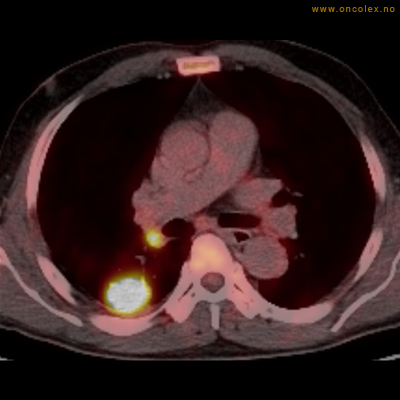

Eksempler på funn

Vev som tar opp mer radioaktivt stoff, synes som hvite områder som lyser opp mer i forhold til annet vev som tar opp mindre sukker.

Kraftig opptak i svulst i lunge.

Lungekreft med spredning til lymfeknute i lungehilus.